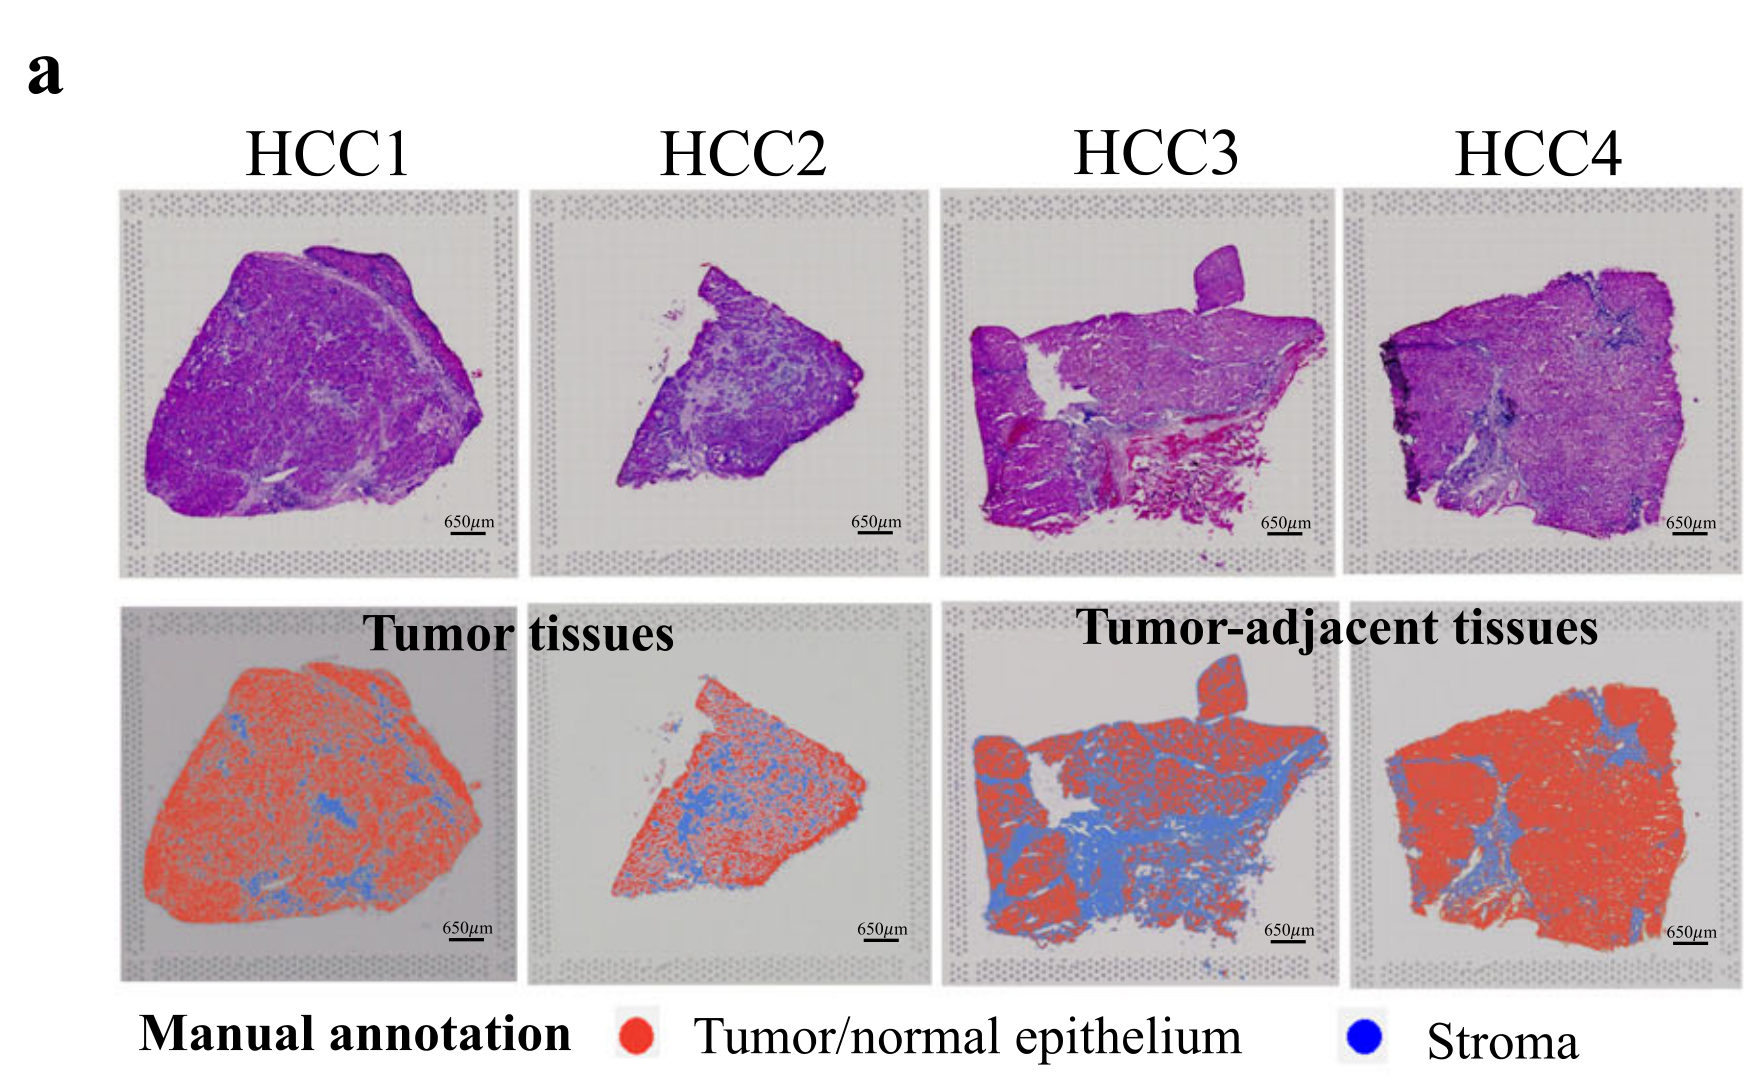

Wei R. et al. - 2022

Spatial charting of single-cell transcriptomes in tissues

Condition Dimension

N/A

Data Components

Biological Annotation

Data

Metadata

None

Modality

Sequencing-based

Resolution of observation

Functional tissue unit

Visualized Elements

Observation

Biological

Tissue

Abstraction

None

Chart Type

Histological image

Communicative/Contextualization

Annotation

Comparative Design

None

Layout

Spatial : Physical

Scalability Strategy

None (Item-level)

Where are tumor regions located within the spatial architecture of a tissue section?